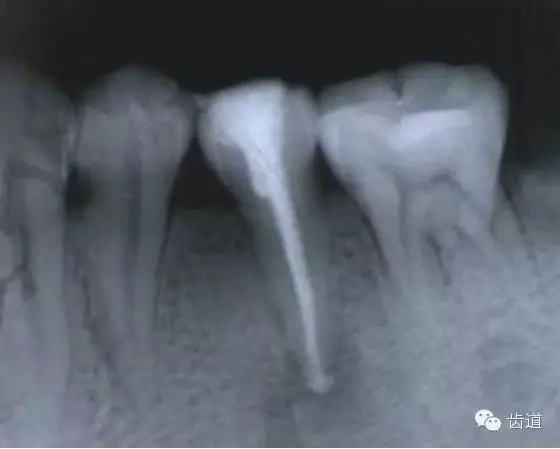

左上7近中頰根器械折斷

右上6腭根器械折斷

折斷于根管內(nèi)的器械要盡量取出,若無(wú)法取出經(jīng)常規(guī)充填后,成功率不受明顯影響。

1.折斷器械有一部分露在根管口外,用鑷子或持針器夾取出。

2.器械斷端在根管口內(nèi):用超聲根管銼在該器械旁增隙,通過(guò)超聲震蕩和沖洗,可將折斷器械從根管內(nèi)震動(dòng)沖出。在手術(shù)顯微鏡下直視操作,大大提高了取出的成功率。

3.折斷器械尖端已超出根尖孔:無(wú)癥狀不處理;有疼痛則作根尖手術(shù)取出。

4.折斷器械較長(zhǎng),各種方法均不能取出,可作根管電解消毒,塑化治療或塑化劑處理,根管充填。

若患牙根尖有病變,必要時(shí)作根尖切除+倒充填。